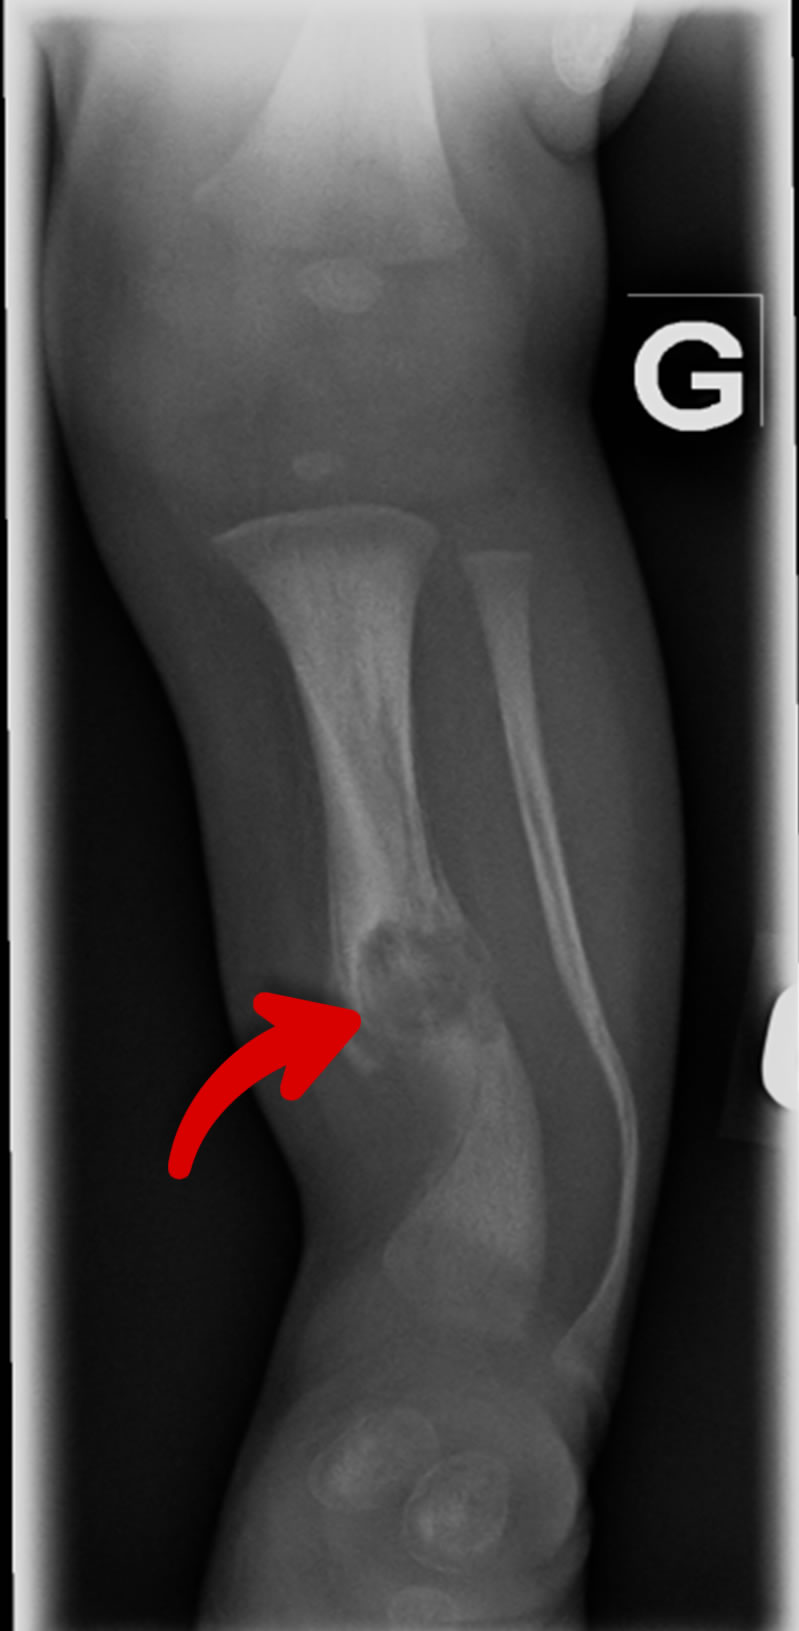

Une dysplasie des os (malformation) peut être présente chez un faible pourcentage de patients avec NF1 (moins de 5%). Cette malformation est habituellement visible dès la naissance et touche habituellement les os de la jambe ou d’une partie de l’orbite.

Si une dysplasie est présente, un suivi étroit avec les orthopédistes est habituellement mis en place. Ces patients présentent un risque élevé de fracture et la guérison est souvent difficile créant une pseudoarthrose.